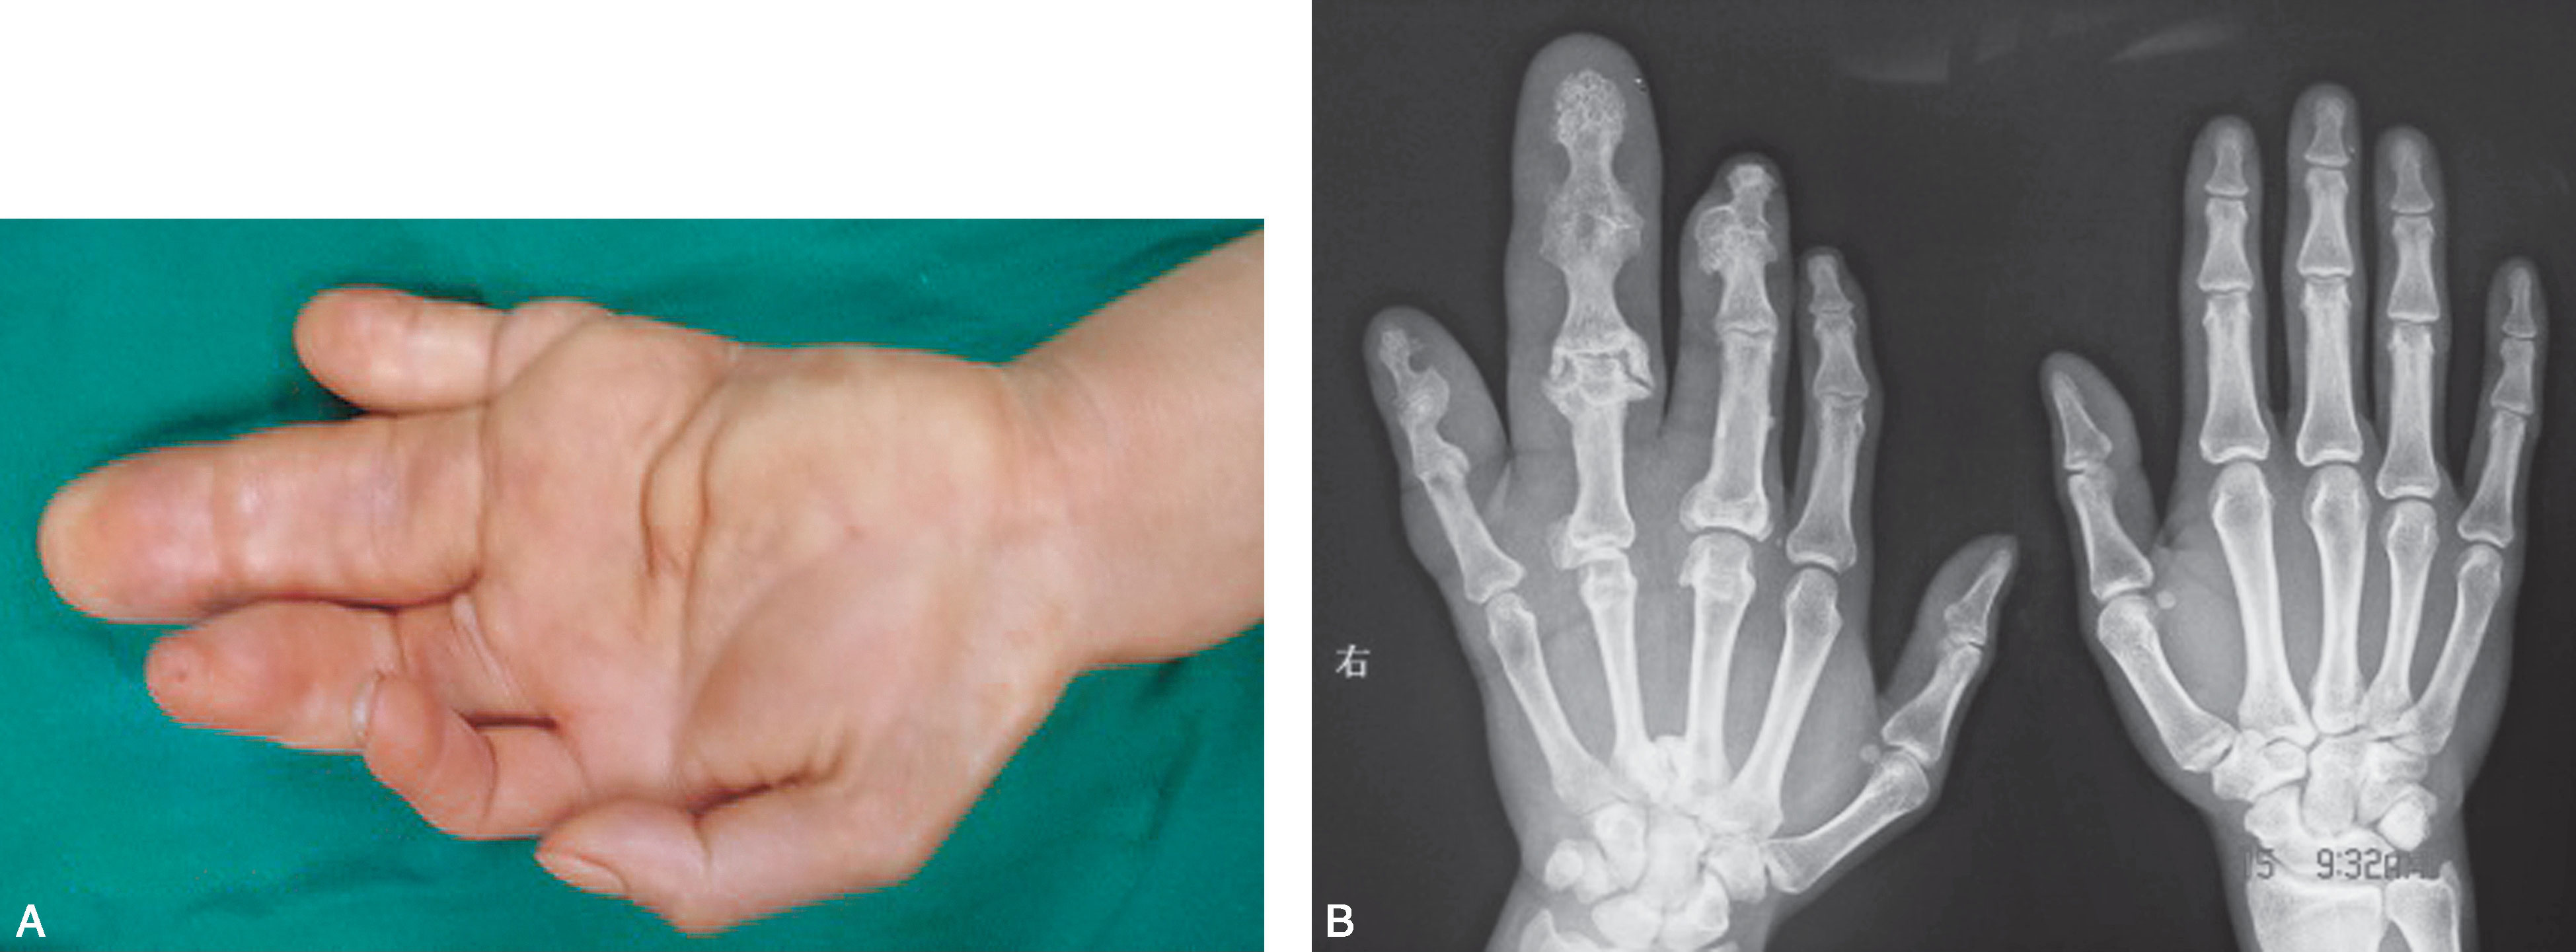

图1-2-29 指间关节融合

图1-2-30 指间关节融合X 线片

先天性双手指间、掌指关节纤维性(或软骨融合)融合